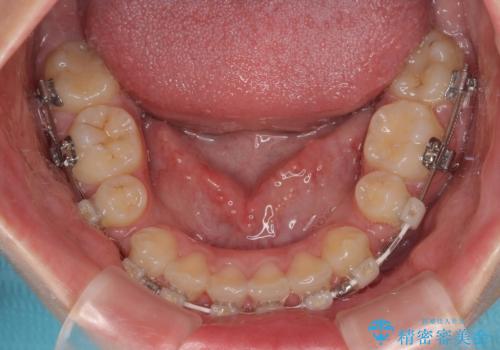

- 下唇の上に乗っかってしまうくらい前歯が飛び出していることを気にして来院された患者様です。

唇を閉じようとするとオトガイ部に力が入ってしまい、うまく閉じることができない状態であったため、上下左右の第一小臼歯4本を抜歯して、ワイヤー装置にて矯正治療を行うこととしました。

飛び出した前歯はしっかりと引っ込み、横顔の印象が大きく変化しました。